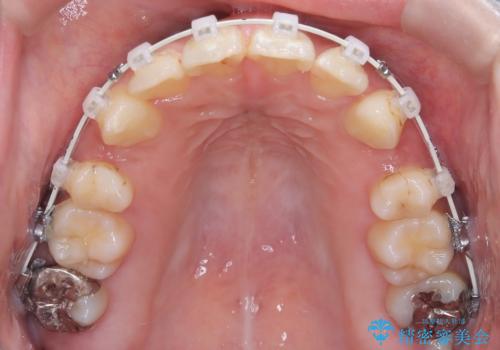

- 矯正装置

- 審美ワイヤー

- 口元が出ていること(突出感)を気にされ、これを下げたいという主訴でご来院されました。精密な検査の結果、前歯を大きく後退させ、口元を改善するためには、スペースの確保が不可欠と診断しました。そこで、上下左右の第一小臼歯(4番目の歯)を計4本抜歯し、そのスペースを利用して前歯全体を奥へ移動させる抜歯矯正の治療計画を立案。確実な歯の移動を実現するため、ワイヤー矯正装置を使用しました。

今回の矯正治療では、口元の突出感を解消するためのスペースを確保するため、計画通り上下左右4本の小臼歯を抜歯しました。装置には、確実な歯の移動と細やかな調整が可能なワイヤー矯正を採用。抜歯によってできたスペースを最大限に利用し、前歯を奥へ、そして垂直的に慎重に移動させました。